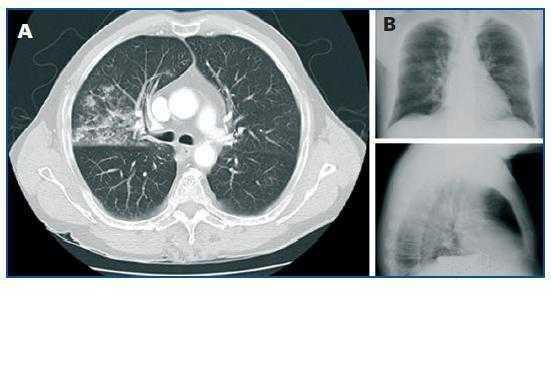

Se realizó una analítica sanguínea que mostró una hiponatremia grave de 115 mmol/l con hipoosmolalidad plasmática de 243 mOsm/kg e hipouricevolumia de 2,4 mg/dl, siendo la caliemia y la función renal normales. Existía en orina una elevada pérdida de sodio de 148 mEq/l. Asimismo, se descartó la existencia de hipotiroidismo e insuficiencia suprarrenal. Orientándose el caso como SIADH, se estableció una restricción hídrica y la administración endovenosa de sueros hipertónicos, existiendo una mejoría progresiva de la hiponatremia y normalización del estado cognitivo. Buscándose la causa del SIADH, se realizó una RMN cerebral sin hallazgos destacables y una TAC torácica que mostró un aumento de densidad de características alveolares limitada a segmentos basales del lóbulo superior derecho, muy sugestivo de neumonía (figura 1A). No obstante, se había realizado una radiografía de tórax al ingreso que no mostraba cambios significativos respecto a controles previos (figura 1B), la auscultación respiratoria fue anodina y no existían leucocitosis ni otros parámetros analíticos sospechosos de infección. Tan sólo destacó durante su estancia hospitalaria una febrícula ocasional de 37,2-37,4 ºC. Por ello, se inició levofloxacino oral realizándose a los seis días nueva TAC torácica que evidenció una importante mejoría de la neumonía. Los antígenos urinarios para Legionella y Neumococo fueron negativos. Progresivamente, fue posible la retirada de sueros hipertónicos, continuando al alta tras 15 días del ingreso con la restricción hídrica, 6 g diarios de sal oral y 10 mg/día de torasemida, permaneciendo los niveles plasmáticos de sodio estables en 131 mmol/l. En el seguimiento ambulatorio, se retiraron los aportes de sal y diurético, evidenciándose al mes del ingreso una completa resolución del SIADH con sodio plasmático de 136 mmol/l.

Figura 1.